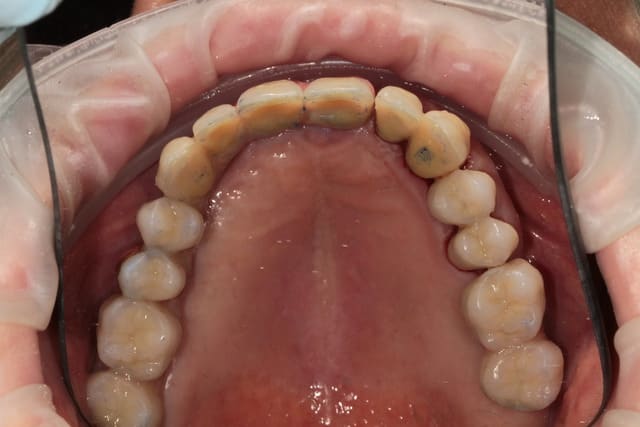

barre transvissée, chapes télescope, fausse gencive céramique au contact gingival et fausse gencive résine au collet des dents.

est-on sensés voir la liaison céram/résine sur la première photo ? si oui re-respect ....

sur les photos il s'agit bien de la liaison céram/résine c'est simple, pour le moment la limite ne se voit pas.